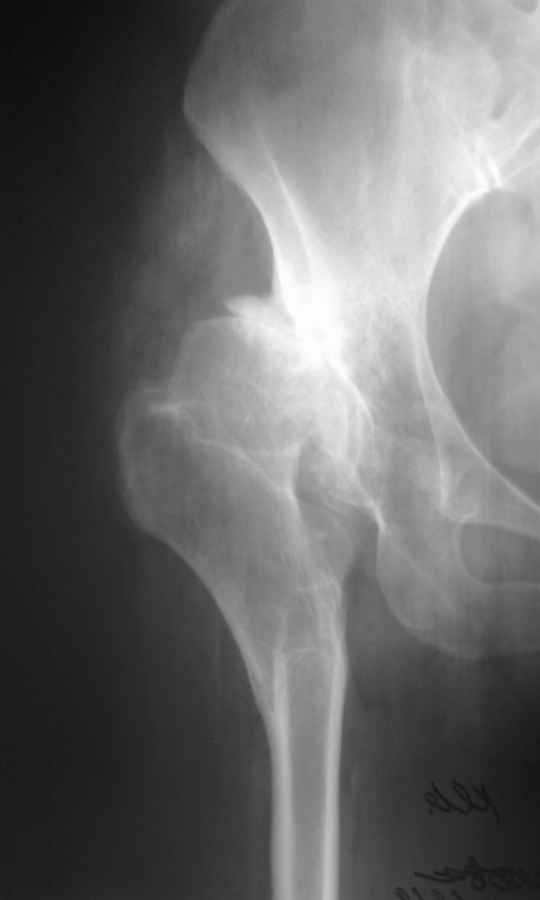

Уважаемый Андрей, ситуация не простая, нет обзорной Р-графии таза, поэтому сложно провести правильное планирование операции. Тем не менее, при планировании операции вертлужный компонент я бы установил в анатомическое положение. В отношении ножки - может быть два решения. Мое предпочтение - (операция типа Paavilaanen'a) поперечная остеотомия бедра на уровне чуть выше деформации, установка ножки Вагнера, скорее всего 190 мм, хотя возможно удастся обойтись и конической ножкой, это зависит от необходимой компенсации длины ноги. Продольная остеотомия б/вертела с последующей фиксацией к диафизу бедра с натяжением мышц. Есть и другой вариант - укорачивающая остеотомия в зоне деформации бедра с установкой ножки со стороны шейки. Мы делали и то и другое, первый вариант проще. В этой операции есть масса нюансов и нужно иметь опыт операций при дисплазии ТБС.

Уважаемые коллеги, без Р-граммы таза нельзя рекомендовать что-н.конкретно, представьте себе, что второй сустав находится в анатомическом положении,тогда позиция шейки протеза на оперируемой стороне будет примерно на уровне малого вертела, и тогда вам придется так укоротить б/вертел, что вы можете остаться без него.... Это очень не простые операции и нельзя без оценки всего таза что-н.советовать, во всяком случае мне так кажется

Уважаемый Андрей! Действительно сложно спланировать операцию без обзорного снимка таза, а так же рентгенограмы бедра в аксиальной проекции. По поводу реконструкции бедренной кости могу предложить следующие варианты опробированные на практике (если есть необходимость пришлю Р-граммы).

-Клиновидная остеотомия бедра на вершине деформации, с углом открыты внутрь. Это позволит выпрямить бедро, добиться полной адаптации обоих фрагментов. Использование ножки Вагнера не позволит фиксировать проксимальный отломок и потребуется какая то дополнительная фиксация, возможно пластиной.

-То же самое с использованием ножки Helios (Biomed) позволит выполнить вполне качественный остеосинтез (ножка из двух частей и позволяет оптиально зафиксировать оба фрагмента), к тому же с возможностью блокирования. Поэтому дополнительной фиксации не потребуется.